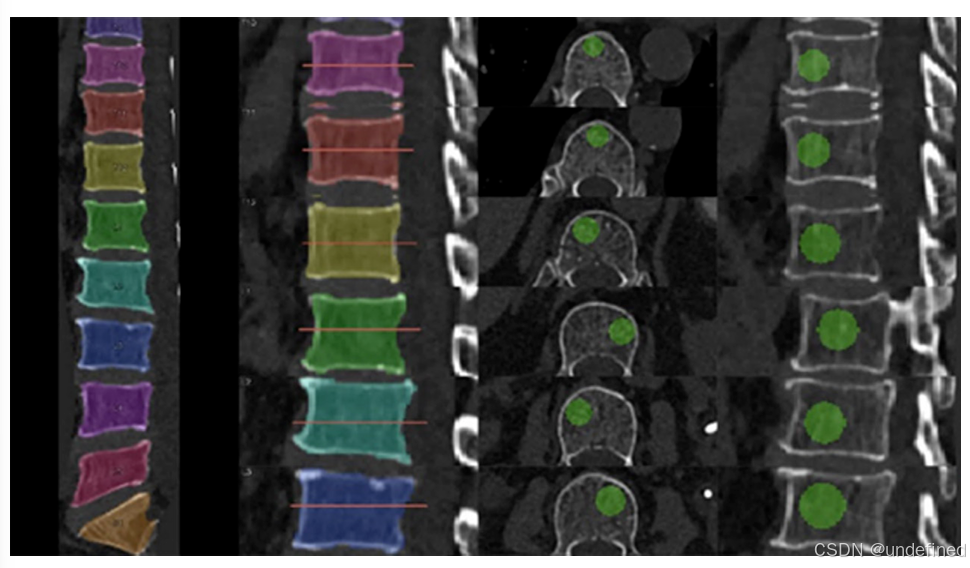

3D vs 2D: 不同于传统的单层2D ROI,该算法自动计算椎体体积,并放置一个体积为椎体5%的球形 3D ROI 。

**定位策略:**ROI自动定位在分割出的椎体内部CT值最低的区域(避开致密骨岛),且位于椎体基底静脉孔的前方。

图1:胸椎和腰椎椎体内3D ROI的放置示意图。